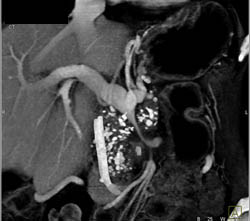

Splenic Tissue Simulates An Islet Cell Tumor